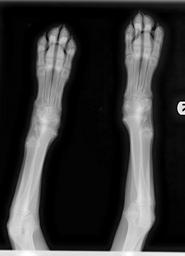

MAKE A MEME View Large Image Hypertrophic Osteodystrophy Weimaraner XRay 2010-12-27.jpg en Hypertrophic Osteodystrophy of the radius and ulna of a 4-month-old Weimaraner puppy Note the moth-eaten appearance of metaphyseal area X-Ray Image of my 4-month-old Weimaraner ...

Keywords: Hypertrophic Osteodystrophy Weimaraner XRay 2010-12-27.jpg en Hypertrophic Osteodystrophy of the radius and ulna of a 4-month-old Weimaraner puppy Note the moth-eaten appearance of metaphyseal area X-Ray Image of my 4-month-old Weimaraner Puppy Image purchased from local veterinarian hospital 2010-12-27 Cc-zero Radiology Radiography Phalanges of the hand